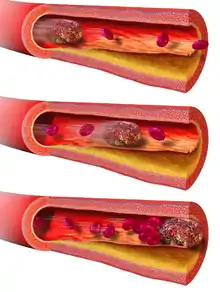

An embolus (/ˈɛmbələs/;[1] pl.: emboli; from the Greek ἔμβολος "wedge", "plug") is an unattached mass that travels through the bloodstream and is capable of creating blockages. When an embolus occludes a blood vessel, it is called an embolism or embolic event.[2] There are a number of different types of emboli, including blood clots, cholesterol plaque or crystals, fat globules, gas bubbles, and foreign bodies, which can result in different types of embolisms.

In contrast to emboli, which can cause occlusion at sites distant from their points of origin, there are also non-traveling blockages that develop locally from vascular trauma and inflammation or other epithelial pathology, such as atheromata and thrombi. If these local blockages dislodge into circulation, they become emboli and if not broken down during circulation, may cause embolism(s).[3] For example, a thromboembolism is the result of a thrombus that has broken off the interior of a blood vessel and caused a vessel blockage elsewhere in the circulation.

In thromboembolism, the thrombus (blood clot) from a blood vessel is completely or partially detached from the site of thrombosis (clot). The blood flow will then carry the embolus (via blood vessels) to various parts of the body where it can block the lumen (vessel cavity) and cause vessel obstruction or occlusion. The free-moving thrombus is called an embolus.[7] A thrombus is always attached to the vessel wall and is never freely moving in the blood circulation. This is also the key difference for pathologists to determine the cause of a blood clot, either by thrombosis or by post-mortem blood clot. Vessel obstruction will then lead to different pathological issues such as blood stasis and ischemia. However, not only thromboembolism will cause the obstruction of blood flow in vessels, but also any kind of embolism is capable of causing the same problem.